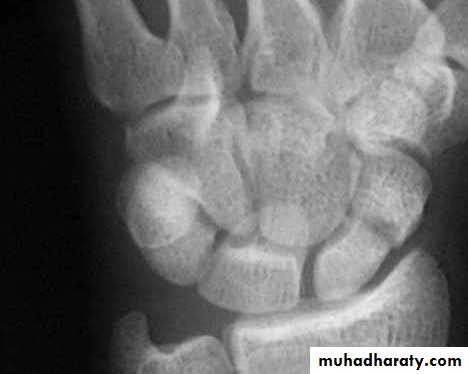

It is caused by fall on out stretched hands ; the most important point in scaphoid is its blood supply inter the bone from distal to proximal direction , so the blood supply is decreased from distal to proximal ; this fact explain why only 1% of the fracture in the distal third of scaphoid , 20% of the fract. In the middle third and 40% of the proximal third fract. Will develop avascular necrosis and non union .Clinically : there is fullness and tenderness in the anatomical snuff box ; other diagnostic sign is that, proximal pressure along the axis of the thumb is painful .

X-ray : a-p , lateral and oblique views are all essentials . Some time recent fracture show it self only in oblique view .

Usually the fracture is transverse and through the narrowest part of the bone (the waist) , but it could be in the proximal pole or in the tubercle ; few weeks after injury the fracture will be more obvious.